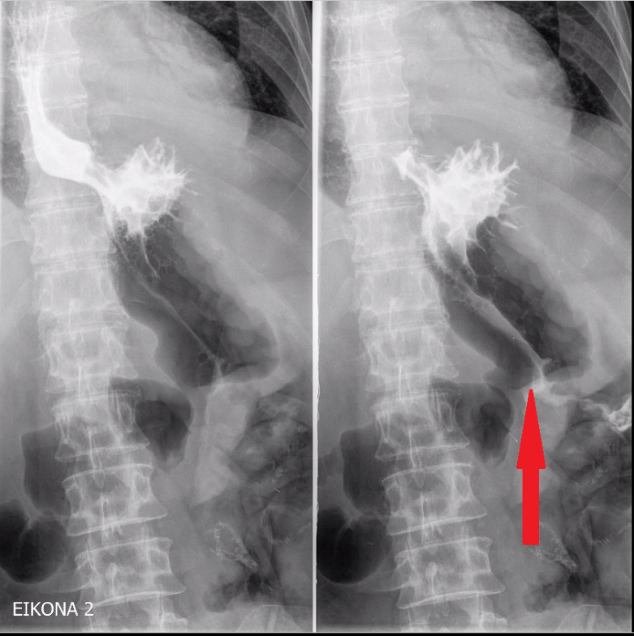

Plain abdominal radiographs. Small bowel loop distension. Red arrow — Radiopaque mass (gallstone) (Courtesy Dr. V. Penopoulos)